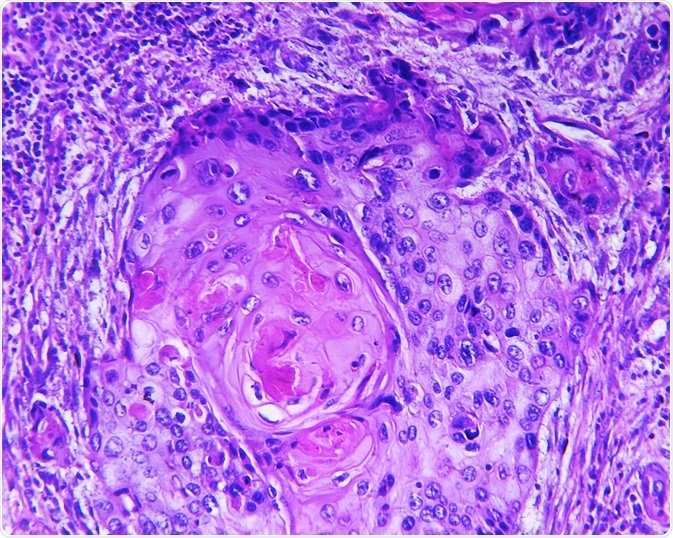

squamous cell carcinomaSquamous cell carcinoma of a human. Image Credit: Designua / Shutterstock.com